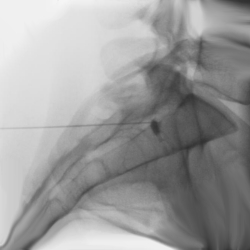

Sacrale Überflutung |

Hier wird mit einer dünnen

Nadel gezielt ein örtliches Betäubungsmittel mit einer geringen Menge

Cortison am Steißbein, weit unterhalb des Rückenmarks, in den Wirbelkanal

infiltriert. Damit können die von dieser Region ausgehenden Schmerzen betäubt und und auch auf Dauer erfolgreich therapiert werden. |